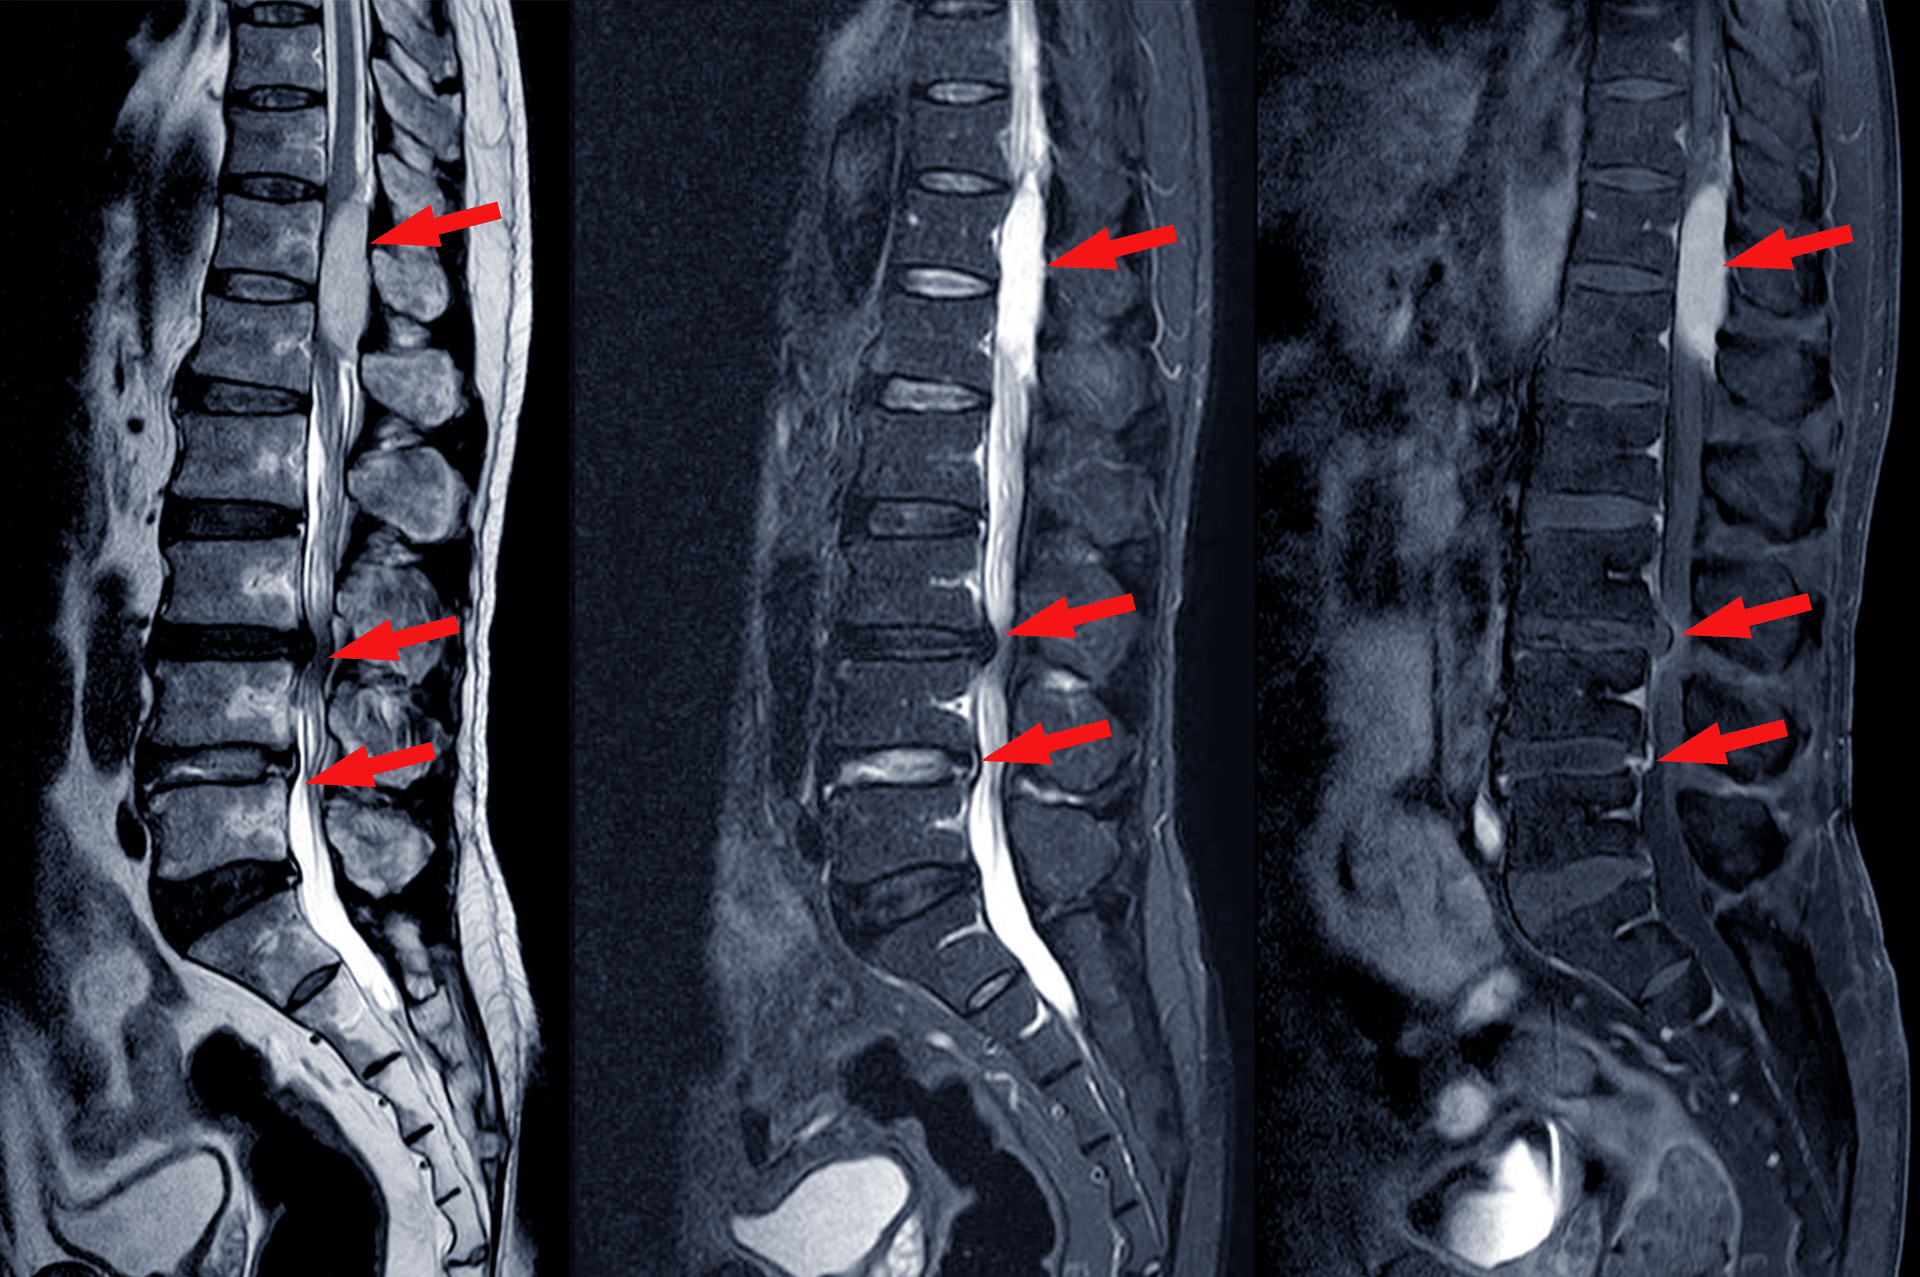

What Is Spinal Stenosis?

Spinal stenosis occurs when the spaces around your spinal cord and nerves become too narrow, compressing the nerve roots and causing pain and other symptoms. It is a common cause of neck and back pain, with cervical stenosis affecting the neck and lumbar stenosis affecting the lower back.